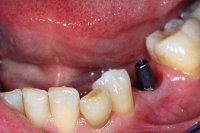

Ein aus der Kindheit stammender Milchzahn ohne Wurzeln im Seitenzahngebiet (Abb. 1), der eiterte und gezogen werden musste, hinterliess bei einer 37 Jahre alten Patientin eine grosse Lücke, aber gesunde Nachbarzähne. Um die Lücke mit einem festsitzenden Zahnersatz zu schliessen, setzen wir ein Zahnimplantat (Abb. 2 und 3). Das Setzen einer Zahnbrücke wäre ebenfalls möglich gewesen, hätte aber das Beschleifen der gesunden Nachbarzähne erfordert, was wir vermeiden wollten.

Sechs Wochen später, nach Einheilung des Implantates (Abb. 2), wird ein Aufbau aus Titan ins Implantat geschraubt (Abb. 3). Nach Abdrucknahme fertigt der Zahntechniker eine Krone an (in diesem Fall eine Vollporzellankrone), die auf dem Implantatpfosten einzementiert wird (Abb. 4). In Abb. 5 ist das Schlussröntgenbild zu sehen.